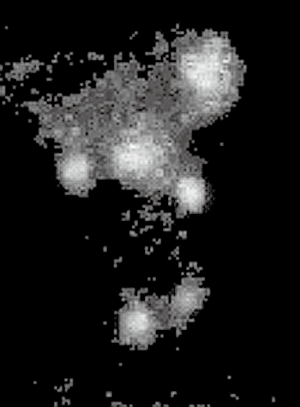

Case 3 was a young woman whose mother had been exposed to radiation in the Chernobyl disaster during her fourth month of pregnancy. As a child she underwent three thyroid and parathyroid explorations in her country of origin. A fourth procedure was performed in a referral Spanish unit and included a right inferior parathyroidectomy, reported as parathyroid carcinoma. Persistent HPT led to a fifth surgical procedure with excision of a cystic parathyroid gland and left thyroid lobectomy. At the time, a mutation in germ-line HRPT-2 was identified and was referred to us with the presumed diagnosis of parathyroid carcinoma with lymph node metastasis in the right lateral compartment II. A SPECT and a neck ultrasound (US) disclosed a hypoechoic nodule close to the carotid bifurcation (Figure 3). A right UPA consisting in two separate parathyroid adenomas was found and resected. Intraoperative PTH showed a curative descent from 180 to 21 pg/mL. The patient required calcium and vitamin supplementation for six months. At four years she is normocalcemic and her PTH is 20 pg/mL.